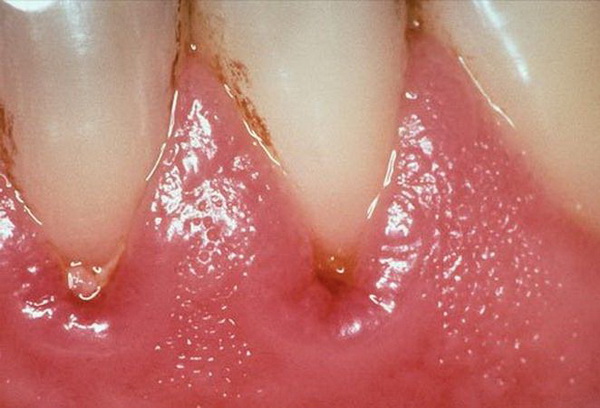

- Образование гингивита и зубного камня. Они возникают при неправильном образе жизни, несоблюдении гигиены ротовой полости;

Врачи отмечают, что опухание верхней десны может быть признаком различных стоматологических проблем. Чаще всего это связано с воспалением десен, которое может возникнуть из-за накопления зубного налета или наличия инфекции. Специалисты подчеркивают важность своевременного обращения к стоматологу, так как игнорирование симптомов может привести к более серьезным заболеваниям, таким как пародонтит. Кроме того, врачи рекомендуют обратить внимание на гигиену полости рта и регулярные профилактические осмотры. В некоторых случаях опухоль может быть связана с аллергическими реакциями или травмами, поэтому важно провести полноценную диагностику для определения точной причины и назначения адекватного лечения.

Такое возникновение присуще хроническому периодонтиту или воспалению верхушки зуба. В результате этого необходимо сделать специальный компресс и обратиться к врачу. Симптомы периодонтита:

- Опухоль имеет размер от 5 до 30 миллиметров;

- Боль отдает в висок, глаз и ухо;

- Сильно страдают щеки;

- В центре воспаления может возникнуть отек

Специалисты отмечают, что болезнь возникает в депульпированном зубе. Снять воспаление можно не только хирургическим путем, но и терапевтическим. При втором в десну вводят специальное лекарство, которое в короткий срок снимает отек. Во время хирургического вмешательства срезают верхнюю часть зуба и делают небольшой разрез. Если основа очень сильно повреждена, то зуб попросту удаляют.